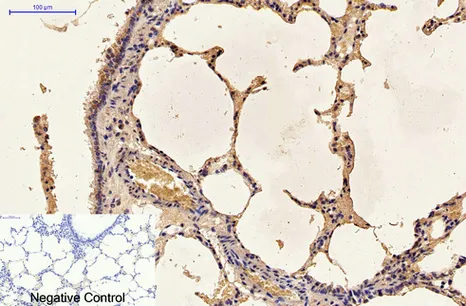

LC3A(5G10)Mouse Monoclonal Antibody

Cat: AMM13240

Size1:50μL Price1:$118

Size2:100μL Price2:$220

Size3:200μL Price3:$380

Application:WB,IF-P,IF-F,ICC/IF,IHC-P

Reactivity:Human,Rat,Mouse

Conjugate:Unconjugated

Optional conjugates: Biotin, FITC (free of charge). See other 26 conjugates.

Gene Name:MAP1LC3A